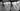

Mezi časté komplikace zubního kazu se řadí zánět dřeně (pulpitida) a rozšíření infekce kořenovým kanálkem až do kostního lůžka zubu (periodontitis). V některých případech mohou být zastiženy i další tkáně v dutině ústní.

Pokud taková situace nastane, je nutné provést endodontické ošetření (vyšetření a ošetření systému kořenových kanálků), během kterého probíhá opracování, čištění, dezinfekce a následné hermetické zaplnění kořenového kanálku.